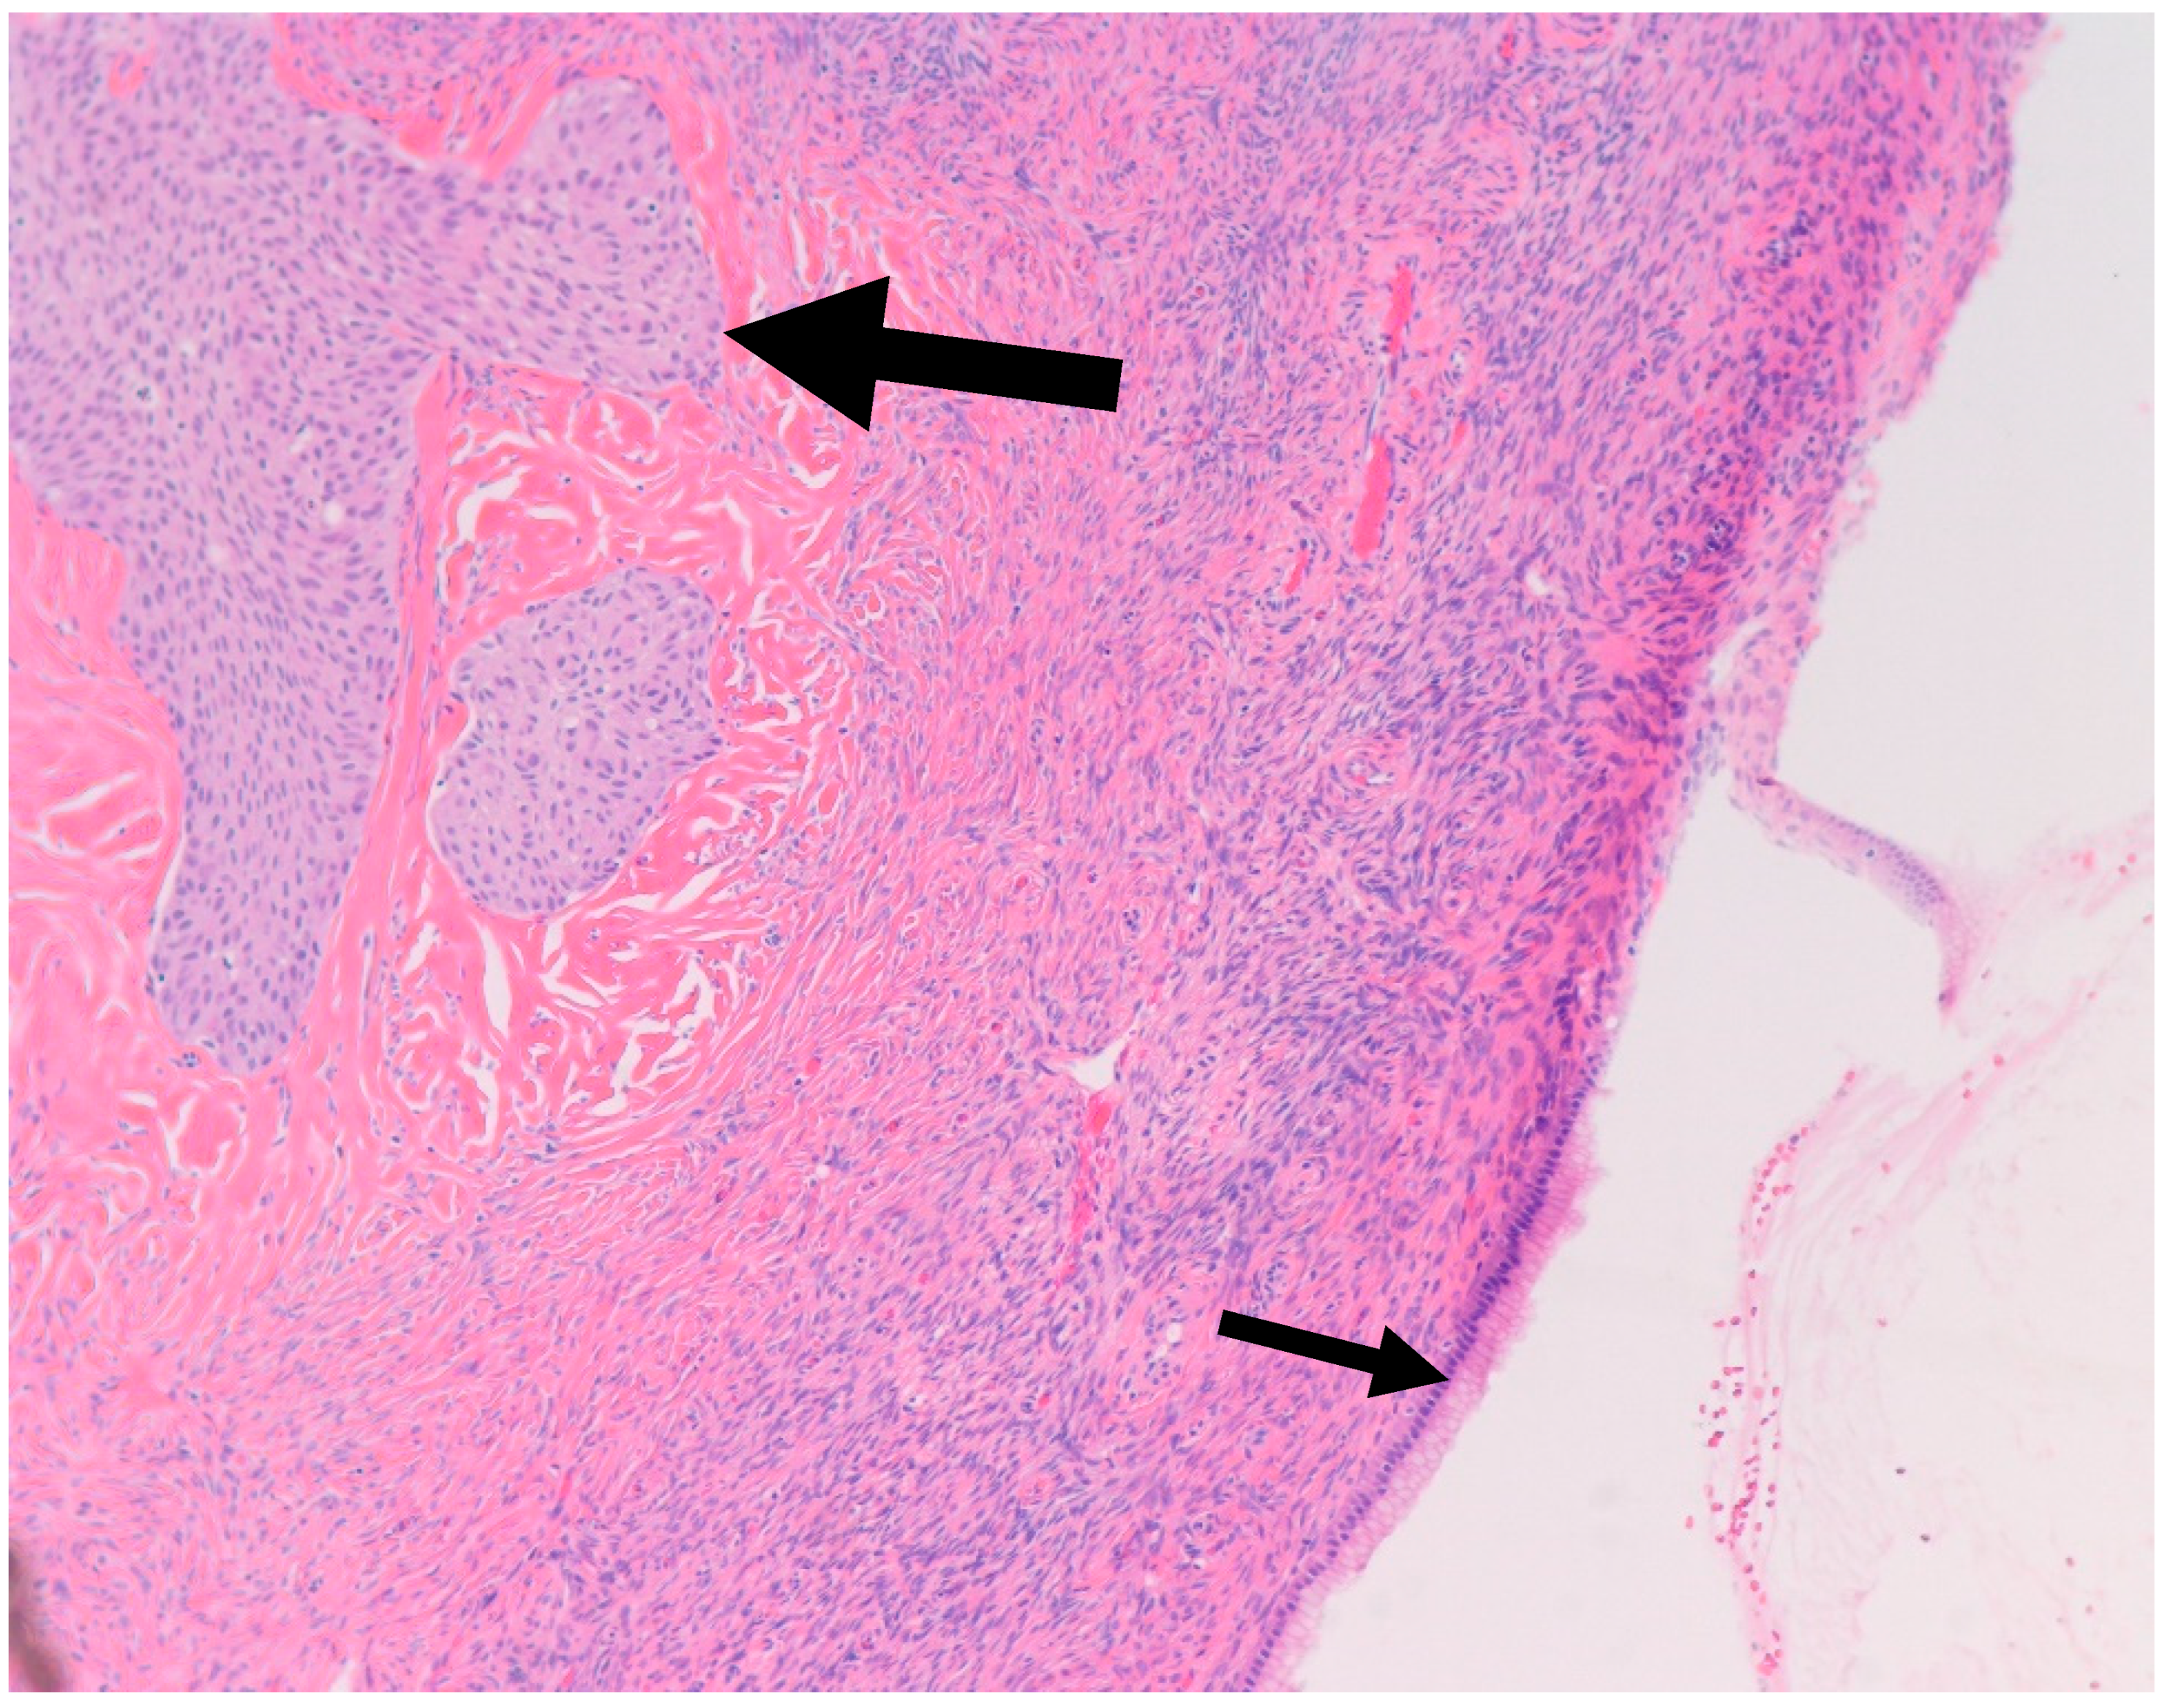

- Walthard cell rests: The differential diagnosis of benign BTs includes Walthard cell rests. Benign BTs contain a fibromatous background which is absent in Walthard cell rests.